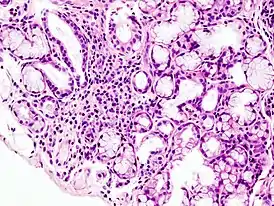

![]() Гистологическая картина локальной лимфоидной инфильтрации малой слюнной железы при синдроме Шёгрена. Биопсия губы. Окраска гематоксилин-эозином. | |

- Биопсия малых слюнных желёз. Обнаруживается инфильтрация слюнных желез лимфоцитами.